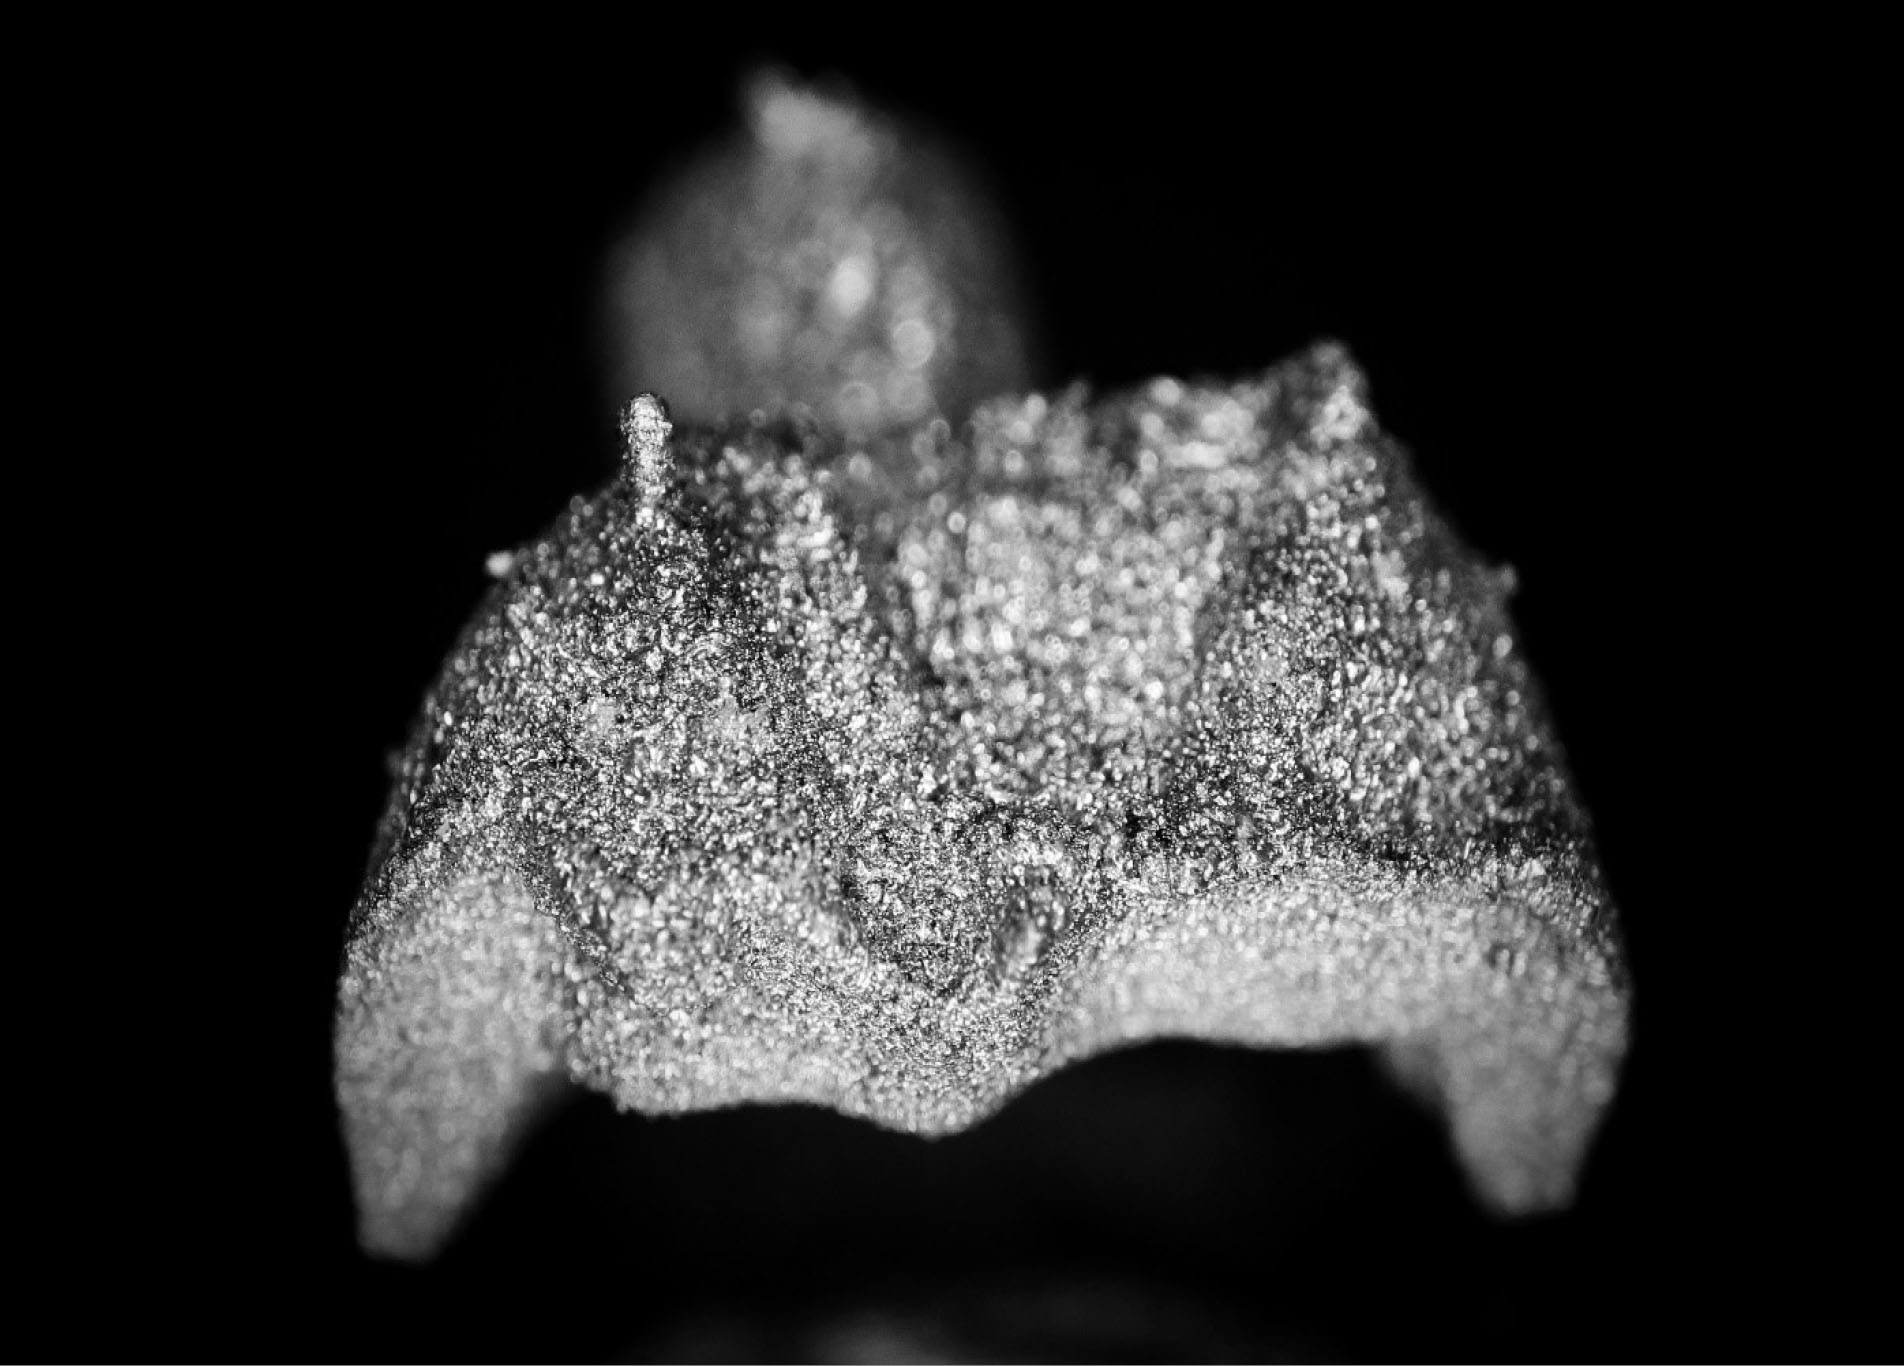

joddd-15-147-g006

Figure 6. Intaglio view of the additive-manufactured onlay.

Three extracted, undamaged human molar teeth were randomly selected from a group of extracted molars. Each tooth was fixed onto a hand-held support. A sectional tray (TempTray; Clinician’s Choice, London, Canada) and provisional material (Template; Clinician’s Choice, London, Canada) were employed to impress each tooth. The teeth were prepared for a four-surface lithium disilicate (Ivoclar, Buffalo, United States) onlay preparation (), as either a mesial-occlusal-distal-lingual (MODL) or a mesial-occlusal-distal-buccal (MODB) onlay. The provisional matrix was filled with a bis-acrylic composite resin (Integrity; Dentsply, Milford, United States) and placed over the prepared tooth. A standard four-surface provisional restoration was then fabricated, shaped, and polished (). The provisional restorations were fixed with a Pic-n-Stic (Pulpdent, Watertown, United States) and coated with titanium dioxide (3M ESPE, St. Paul, United States). The provisional restorations were then digitized (True Definition; 3M ESPE, St. Paul, United States) to create a digital stereolithography (STL) file of the provisional restoration ( and ). The STL files were digitally transferred to ADEISS (London, Ontario). The files were imported with Fusion 360 software (Autodesk, San Rafael, United States) and printed in cobalt-chromium ( and ) with a Renishaw AM 400 Laser Melting System (Renishaw PLS, Gloucestershire, United Kingdom). The printer utilized selective laser melting (SLM) technology, which melted and fused metallic powder layers (with an average diameter of 30‒50 µm) using a 400-W laser. The onlay restorations underwent standard post-processing without polishing.

The digital scanner provided an STL file of suitable resolution for three-dimensional (3D) printing in metal. The indirect onlay restorations were successfully 3D-printed in cobalt-chromium with dimensions, morphology, and fit clinically acceptable for subsequent cementation. Cementation was unremarkable and adequately retained the onlays, similar to previous investigations. 6 Marginal adaption was generally acceptable but was clinically unacceptable in one area due to an open margin. The surface finish was generally acceptable but could be improved in some areas, especially on the occlusal surface.